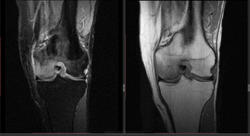

Мужчина 1963 г.р. Жалуется на боль в левом коленном суставе около 6 мес, в последний месяц стало совсем тяжко. Со слов заболел зимой, когда во время прогулки коленки сильно замерзли. Сам думаю на асептический некроз, но смущает множественность поражения.

Дмитрий, я в заболеваниях суставов не дока, но трабекулярный отек вкупе с выпотом может быть обусловлен воспалительными изменениями , но полностью начальные проявления аваскулярного некроза не могу отрицать.

я бы не поставил аваскулярный некроз. если исключена травма, дифференцировать с артритом.

Хрящ не поврежден, для артрита...